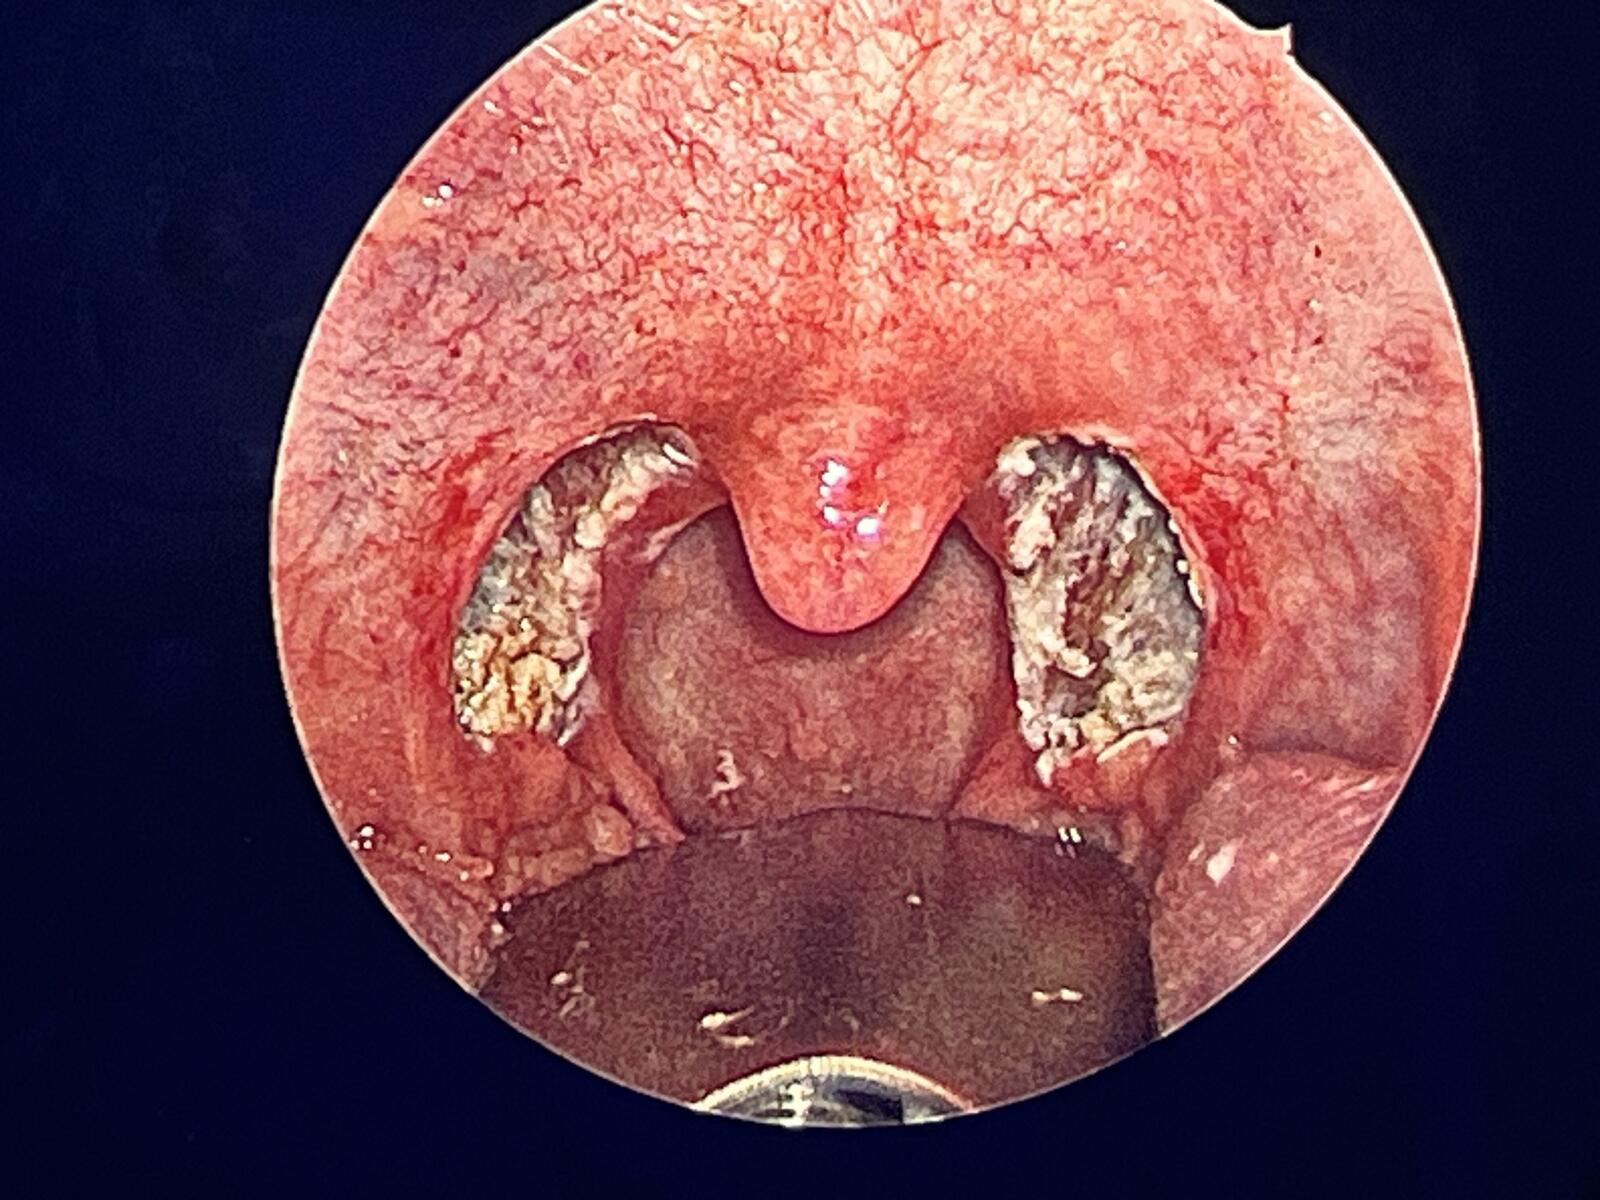

女儿的扁桃体保留双侧下极的1/5

左扁桃体下极保留1/5

母亲手术后的咽腔